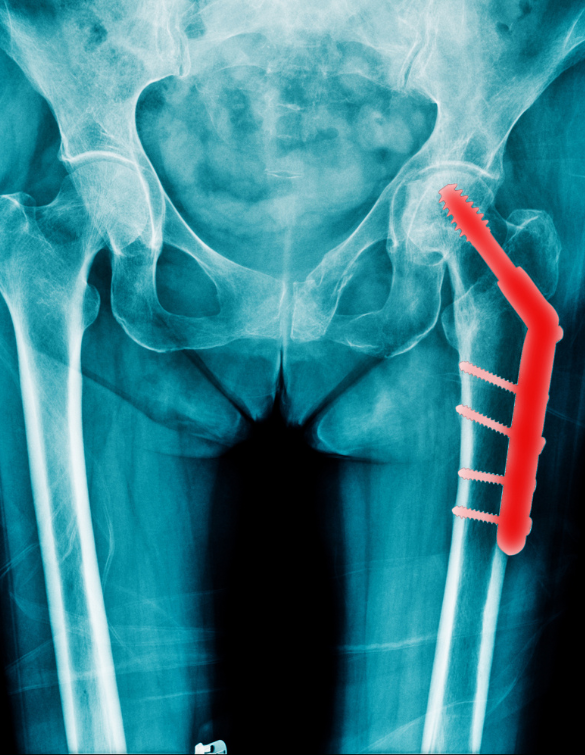

We offer comprehensive care for hip fractures—from diagnosis to surgery and post-operative rehabilitation. The process begins with clinical assessment, X-rays, and sometimes CT scans to evaluate the fracture type. Based on the findings, our orthopedic team develops a tailored surgical plan. Internal fixation is preferred for non-displaced or stable fractures, using metal screws, rods, or plates to hold the bone together.

For displaced or severe fractures—especially in older adults—partial or total hip replacement is recommended. In hemiarthroplasty, the femoral head is replaced with a prosthesis, while in total hip replacement, both the femoral head and hip socket are replaced. These procedures are performed under spinal or general anesthesia with precision and care.